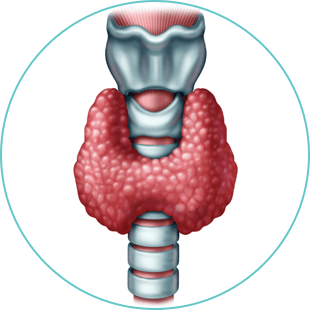

Thyroid

Lorem ipsum dolor sit amet, consectetur adipiscing elit. Etiam nec aliquam ex, eget consequat est.

- Morbi venenatis non lectus sit amet tincidunt

- Gellentesque sit amet eleifend velit

- Vestibulum fermentum cursus facilisis

- Etiam nec aliquam ex, eget consequat est.

Lorem ipsum dolor sit amet, consectetur adipiscing elit. Ut quis libero eros. Vestibulum fermentum cursus facilisis. Pellentesque sit amet eleifend velit. Donec consectetur posuere tortor a finibus.